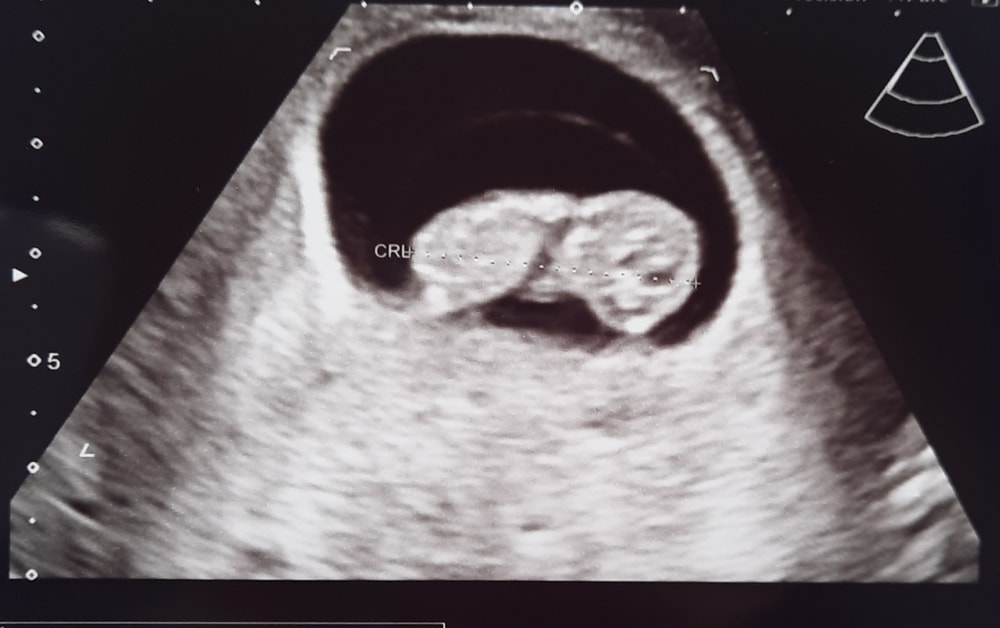

Сегодня по календарю ровно 9 недель, по узи ставят 9+2. Кто рядышком и делал узи на этом сроке - у вас примерно такие же показатели?

Малыш активно танцевал на мониторе, это так мило))) ручку постоянно к голове прикладывал. Через 3 недели на скрининг, а через 2 кровь на пол. Впереди всё самое интересное🥰

П.с. на каждом узи приходится объяснять, что мы не отстаём, а что О (отслеженная) была аж на 30 дц 🙈